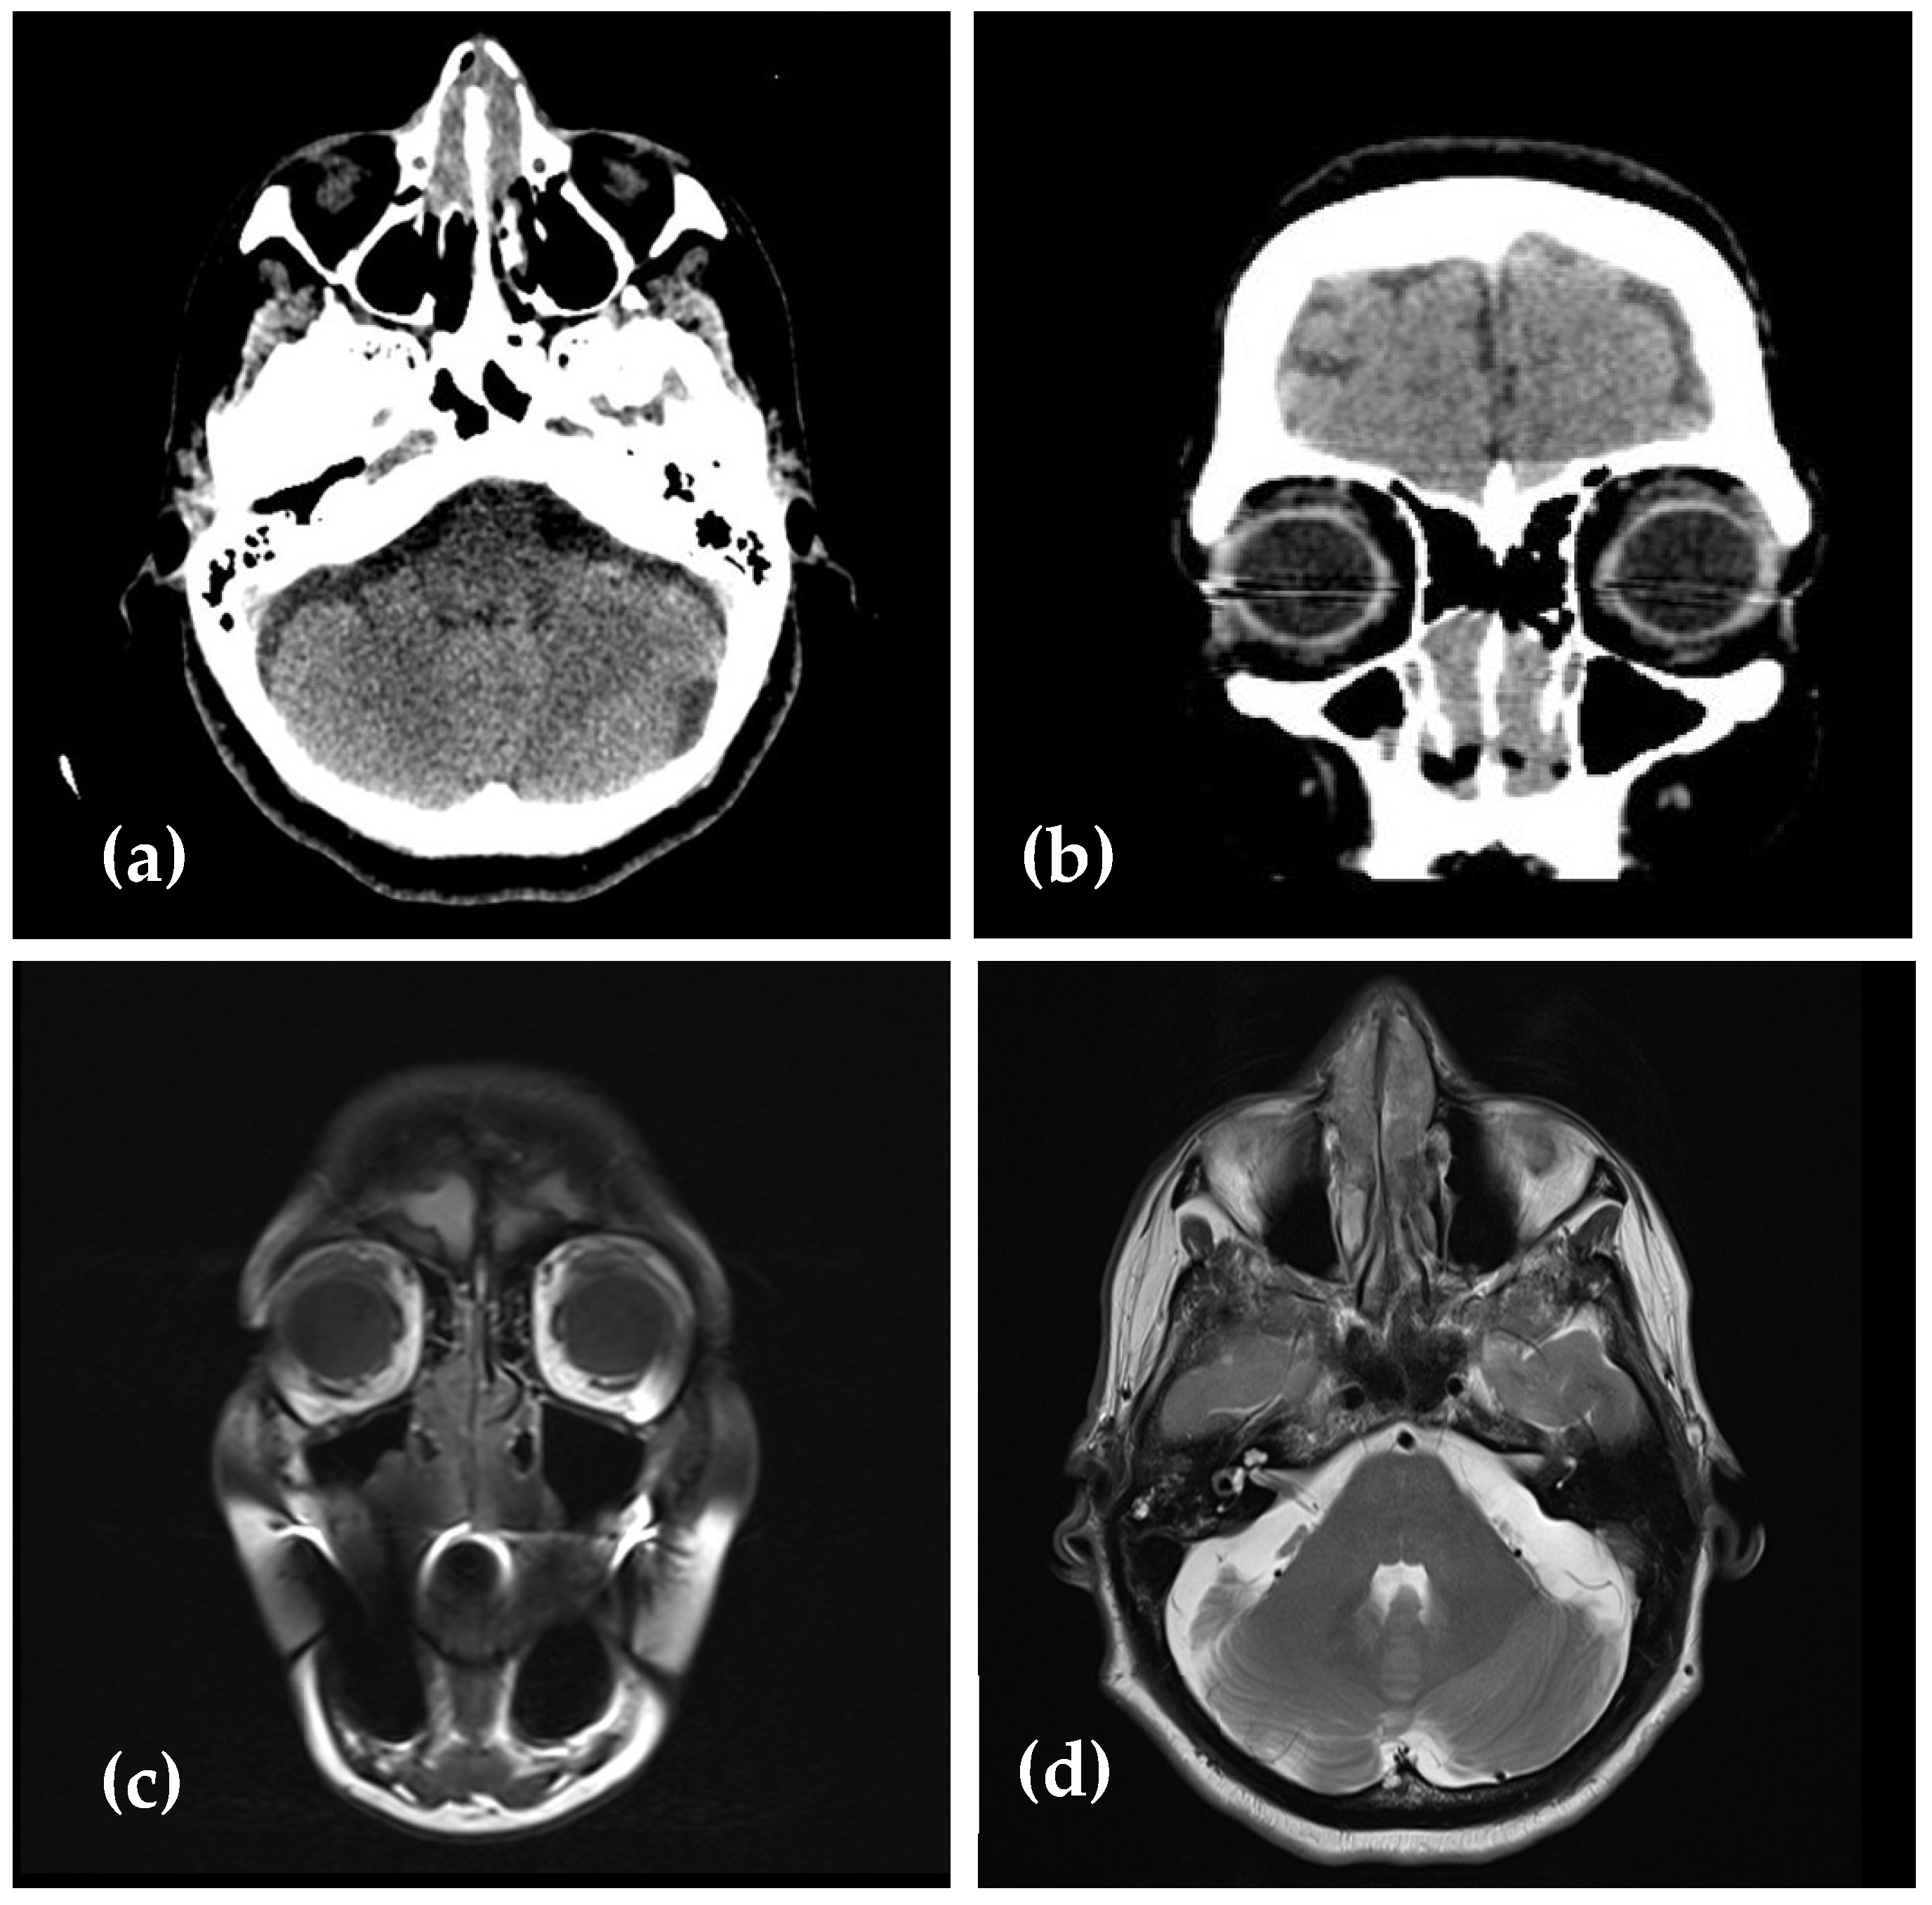

2. Case Presentation